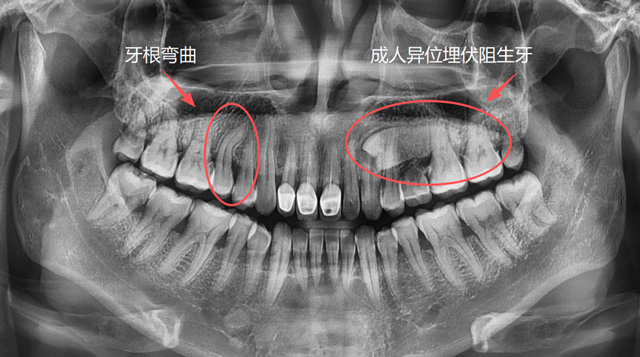

想要让一颗牙脱位,直的牙根是比较好操作的,弯的牙根因为有一定的弧度,需要顺着这个弧度来解除阻力。如果反着用力,可能会造成牙根折断,取断根需要去骨,就会损失一些牙槽骨的骨量。

为什么有的牙可以完整取出,有的牙需要切割成两三块再取出呢?原因就是因为它们的解剖结构和阻力点不同,拔牙手术的方案也有所差异。

成人牙根弯曲、异位埋伏阻生牙

总的来说,医生会根据牙齿的解剖结构和位置等因素去判断阻力,去分析怎么把这个阻力解除,再采用相应的手术方案和工具来完成手术。

问:什么样的牙比较难拔?

刘伟博士:解剖位置、解剖结构异常的牙齿,拔牙难度更大一些。包括位置异常的阻生牙、异位牙,结构异常的如牙根弯曲、牙根多的牙,还有因为长期慢性炎症造成牙周粘连的牙,以及一些完全退缩到骨头里面的残根,都有一定的难度。